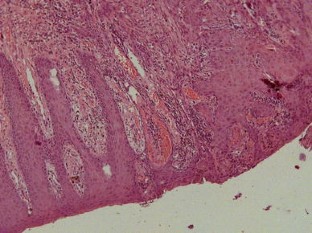

In both patients, the degeneration of mesh infection into SCC was presumably caused by the long-term inflammation secondary to infection. Patients presented with advanced SCC behaving just like the Marjolin’s ulcers of burns. Radical surgical excision was the treatment of choice. The involvement of the bowel played an additional challenge in case 1, but it was possible to resect the tumor and the involved bowel and reconstruct the abdominal wall using polypropylene mesh as onlay reinforcement, in a single stage operation. He is now under adjuvant chemotherapy. The big gap in the midline after tumor resection in case 2 required mesh bridging to close the defect. The poor prognosis of case 2 who died months after the operation, and the involvement of the armpit, groin and mesenteric nodes in case 1 shows how aggressive this disease can be.

Fig. 3

Fig. 4